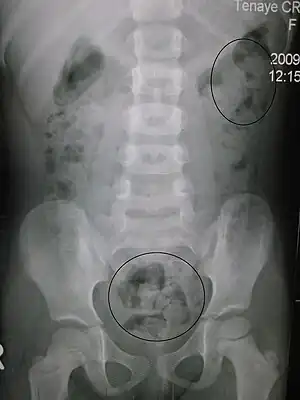

| Constipation in a young child seen on X-ray. Circles represent areas of fecal matter (stool is white surrounded by black bowel gas). | |

Abdominal X-rays are generally only performed if bowel obstruction is suspected, may reveal extensive impacted fecal matter in the colon, and may confirm or rule out other causes of similar symptoms.[22][15]